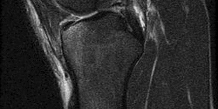

Figures 1 and 2 are intrasurgical photographs from the posterolateral viewing portal that were taken at the beginning and end of a right shoulder arthroscopic procedure performed on a 54-year-old man. This technique demonstrates superior results compared with traditional arthroscopic techniques when evaluating which outcome? ---

The images reveal a medium-sized tear of the rotator cuff. As more clinical studies are published comparing double-row with single-row rotator cuff repair, it has become clear that the retear rate is lower with a double-row construct for small and medium-sized tears. This may be attributable to the stronger time-zero repair construct that double-row repair provides. No study to date has demonstrated a significant difference in clinical outcomes (functional and pain scores at any time) or time to healing between the two techniques.